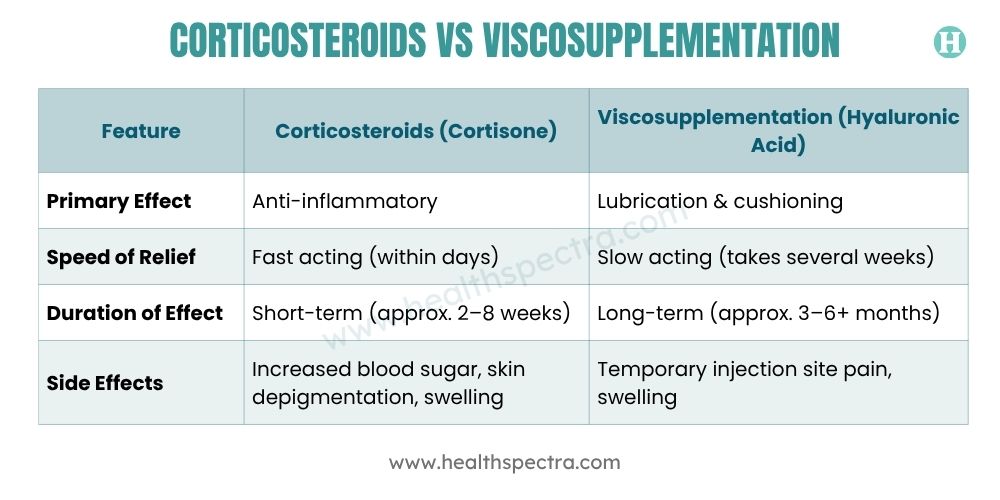

Corticosteroids vs Viscosupplementation — Side-by-Side Comparison

It’s not always easy to decide between a cortisone shot vs hyaluronic acid. Each injection serves a different purpose in OA management.

When you’re dealing with knee osteoarthritis, everyone’s looking for ways to ease the pain and put off surgery as long as possible. Two options often come up: corticosteroid vs viscosupplementation injections. They work differently, but both can help people stay active and manage their symptoms.

Corticosteroid shots come in handy when pain suddenly flares; they kick in quickly, knocking down both pain and swelling. Viscosupplementation takes a different approach, focusing on lubricating the joint. Some people find this gives them relief that sticks around longer.